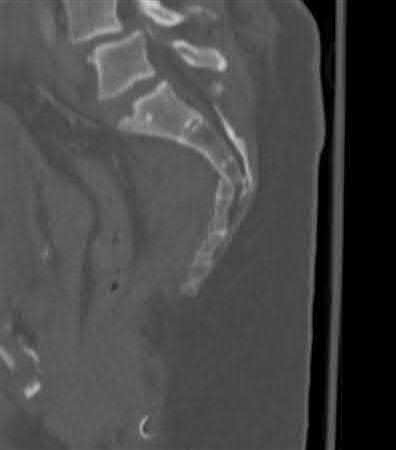

A 35 year-old female presents after prolonged extrication from a motor vehicle collision complaining of severe pelvic pain. Physical examination reveals diminished perianal sensation. She is otherwise neurologically intact. Figures A through D are radiographs and representative CT cuts of her injury. Which of the following nerve roots has likely been injured by the acute trauma?

The clinical scenario is consistent with a high-energy sacral fracture. The radiographs in figures A and B demonstrate a sacral fracture with posterior displacement of the right hemipelvis seen on the inlet view. Figures C and D are axial and sagittal CT images which show a displaced fracture of the right

hemisacrum along with a transvere fracture component through the S3 body . Diminished perianal sensation is concerning for an S2 nerve root injury.

Mehta et al reviewed the current management of sacral fractures. They note that the S1 and S2 nerve roots are more likely to be injured with sacral fractures as they occupy 1/3 to 1/4 of the neural foramina, as opposed to S3 and S4, which only occupy 1/6 of the neural foramina.

Robles reviewed the current literature to ascertain principles of evaluation and treatment for transverse sacral fractures. The author notes that injury to nerve roots S2 to S5 is manifested by impairment of urinary and anal continence and sexual function.